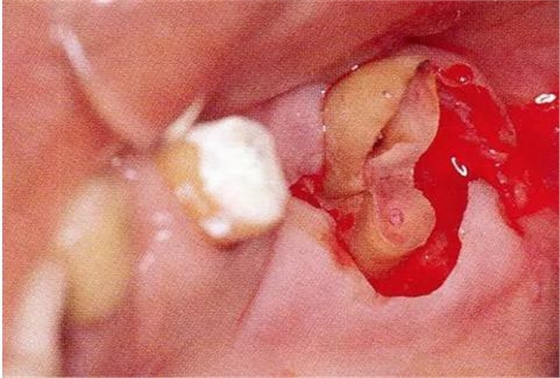

▼圖16-4

圖16-4進(jìn)行牙齒分割時(shí),如圖所示一樣,要確保分割去除的牙根邊緣不會(huì)殘留在牙槽中間骨脊。如果有邊緣殘留,會(huì)造成軟組織發(fā)紅,引發(fā)炎癥。

▼圖17

圖17將右上6近中頰側(cè)根拔除,考慮到修復(fù)物清潔性的情況下進(jìn)行備牙。牙齒分割后如果有邊緣殘留,就會(huì)使切割面的牙齦發(fā)紅無法治愈。